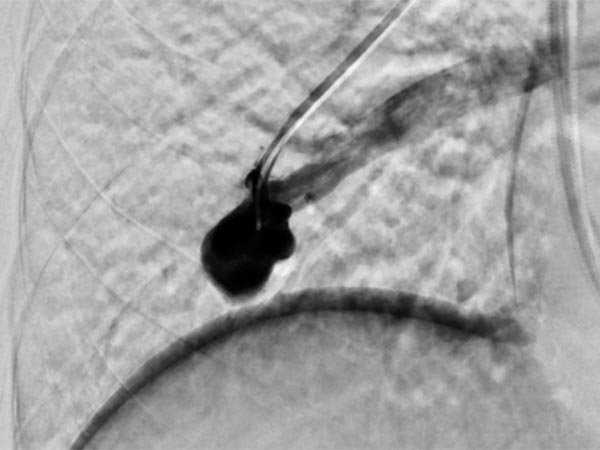

Bei der Abklärung der Grunderkrankung wurde in der Kontrastmittel-Sonographie ein pulmonaler Rechts-links-Shunt gefunden, die Computertomographie bestätigte den Befund mehrerer pulmonaler AVM. Aufgrund der Größe, Indikation zur Embolisation. Die digitale Subtraktionsangiographie zeigt eine bereits superselektiv kanülierte pulmonale AVM im Oberlappen mit der typischen aneurysmatisch erweiterten arteriovenösen Kommunikation.

Nach Sondierung der größeren pulmonalen AVM zeigt sich ebenfalls eine für den Morbus Osler typische Dilatation der direkten arteriovenösen Kommunikation in Form eines Aneurysmas. Der venöse Abstrom ist stark dilatiert, damit ist die Gefahr einer Embolie besonders groß.

Die zuführenden Arterien werden mit mehreren Coils verschlossen. Zur sicheren Verankerung werden Teile der Coils in die arterielle Aufzweigung gelegt (Anker-Technik). Die pulmonale AVM ist verschlossen. Im ehemaligen Aneurysma steht noch etwas Kontrastmittel von einer vorherigen Injektion.